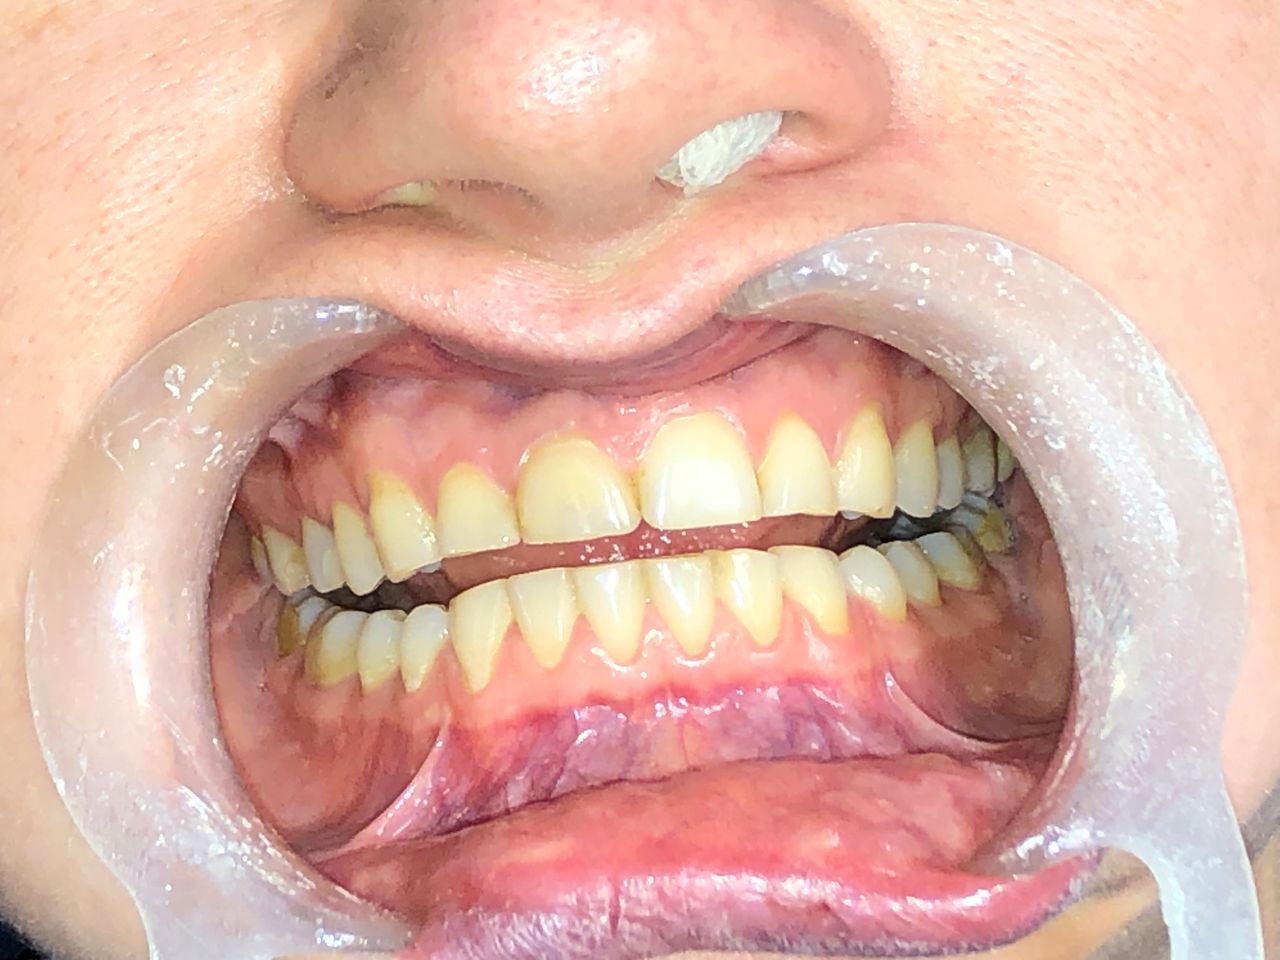

Foto e video

• M

Il Dottor Luca Strazioso ha qualità rare; mi ha ascoltata attentamente sin dal primo appuntamento, con la sua pazienza, competenza e professionalità durante ogni seduta ha ricostruito il mio sorriso, mi ha ridato la sicurezza che ormai avevo perduto. Posso affermare di essere rinata grazie alle sue mani, alla sua intelligenza e sensibilità. Inoltre, la Signora Antonella, assistente alla poltrona, è assolutamente insostituibile e generosa. Infinitamente grata ad entrambi.

• Studio Dentistico LUCA STRAZIOSO implantologia  •